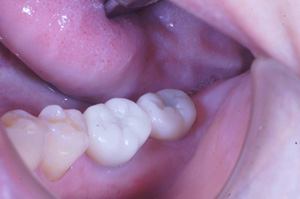

@@R.S‚³‚ñ@56Î —«  ‘åŠw‹³Žö @Žèp“ú@‚Q‚O‚O‚W”N ‚QŒŽ ‚X“úi“yj@㉺Š{  ƒm[ƒxƒ‹ƒKƒCƒhŽg—p@Ö¬“à’ÁÖ@•¹—p@@@

@@@@@ãŠ{  All on ‚U@‘¦Žž‰Ád@@

@@@@@@@@@@@@@ Rpl Tapered Rp  ‚P‚O mm(‚U–{)

@@@@@‰ºŠ{¶‰E@‘¦Žž‰Ád@ ‚R Unit Bridge@

@@@@@@@@@@@ @Rpl Tapered Rp  ‚P‚O mm(‚S–{)@@–ƒWƒ‹ƒRƒjƒAƒNƒ‰ƒEƒ“‚ÅÅI•â’Ô